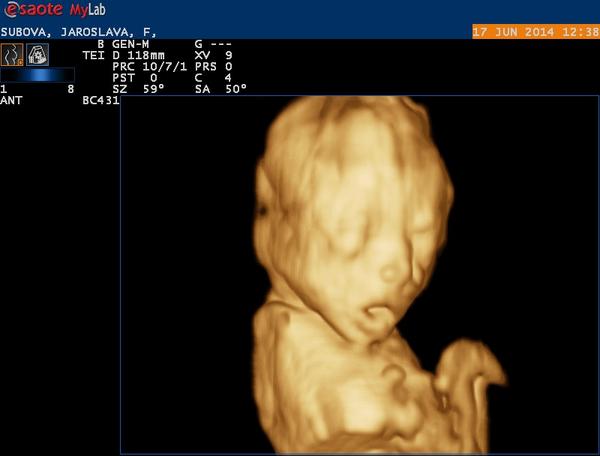

Najmilsi moment bol asi ten, ked aj moj muz pocitil pohyby babatka po prvykrat - jeho prekvapenie a vyraz v tvari. Najemotivnejsi, ked som nasla dve ciarky..a taky celkovo milovesely, ked sme na ultrazvuku videli babo obaja - nespalo, rozhadzovalo ruckami a kopalo🙂